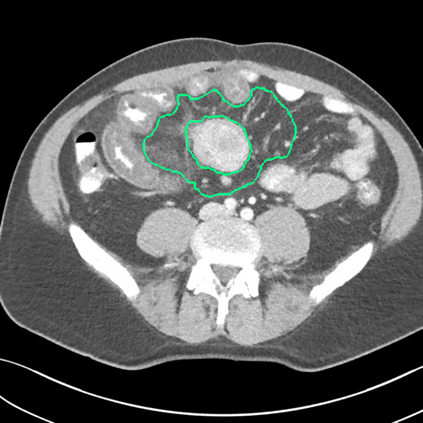

Radiomics uses quantitative medical imaging features to predict clinical outcomes. Currently, in a new clinical application, finding the optimal radiomics method out of the wide range of available options has to be done manually through a heuristic trial-and-error process. In this study we propose a framework for automatically optimizing the construction of radiomics workflows per application. To this end, we formulate radiomics as a modular workflow and include a large collection of common algorithms for each component. To optimize the workflow per application, we employ automated machine learning using a random search and ensembling. We evaluate our method in twelve different clinical applications, resulting in the following area under the curves: 1) liposarcoma (0.83); 2) desmoid-type fibromatosis (0.82); 3) primary liver tumors (0.80); 4) gastrointestinal stromal tumors (0.77); 5) colorectal liver metastases (0.61); 6) melanoma metastases (0.45); 7) hepatocellular carcinoma (0.75); 8) mesenteric fibrosis (0.80); 9) prostate cancer (0.72); 10) glioma (0.71); 11) Alzheimer's disease (0.87); and 12) head and neck cancer (0.84). We show that our framework has a competitive performance compared human experts, outperforms a radiomics baseline, and performs similar or superior to Bayesian optimization and more advanced ensemble approaches. Concluding, our method fully automatically optimizes the construction of radiomics workflows, thereby streamlining the search for radiomics biomarkers in new applications. To facilitate reproducibility and future research, we publicly release six datasets, the software implementation of our framework, and the code to reproduce this study.

翻译:放射科使用定量医学成像特征来预测临床结果。目前,在一个新的临床应用中,通过一个超常试验和高压过程,通过人工操作,从广泛的现有选项中找到最佳放射法。在本研究中,我们提议了一个框架,自动优化每个应用程序的放射工作流程的建设。为此,我们将放射作为模块工作流程,并包括每个部件的大量通用算法。为了优化每个应用程序的工作流程,我们使用随机搜索和聚合的自动机学习方法。我们用12种不同的临床应用来评估我们的方法,结果在曲线下应用的以下领域:1) 脂色瘤(0.83);2) 脱氧型纤维瘤(0.82);3 初级肝脏肿瘤(0.80);4 气肠肿瘤(0.77)、5 彩虹肝脏移植(0.61); 6 脑膜细胞变异常(0.45); 7) 肝细胞变异常(0.8) 脑纤维变异位(0.80); 9) 直径直线型癌症(0.74) 和头型癌症(0.77) 直径研究(10) 。